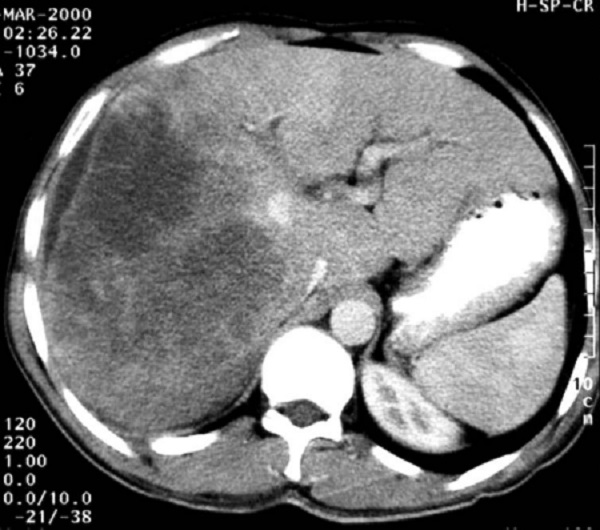

Мрт рака печени

Мрт рака печени 112 фото